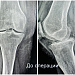

Чтобы избавиться от мучительной боли в колене, наша 55-летняя пациентка готова была избавиться от всего сустава. При госпитализации женщина настроилась на эндопротезирование. Однако травматологи-ортопеды выбрали другую тактику. При вальгусной деформации и деформирующем артрозе второй стадии коленный сустав оставался достаточно сохранным. Чтобы спасти его от замещения металлоконструкцией, была выполнена корригирующая остеотомия.

Суть операции – в исправлении нарушенной оси конечности. После перестроения и выравнивания костей голени нагрузка собственного веса смещается с пораженной части сустава на здоровую. Таким образом, болевой синдром регрессирует, а износ сустава замедляется.

В случае с этой пациенткой ради сохранения коленного сустава пришлось пожертвовать 10 миллиметрами большеберцовой кости. Костный клин такого размера был удалён, чтобы вернуть конечность в правильную механическую ось. Небольшие размеры современных фиксаторов позволяют выполнять операции малотравматичным доступом – через 4-5-сантиметровый разрез.